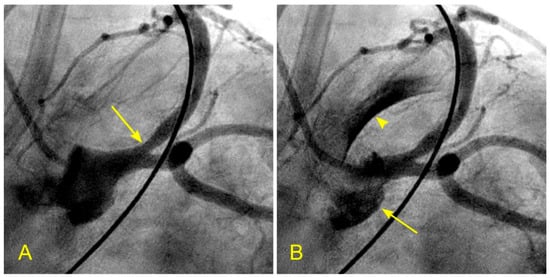

(A,B) Recirculating flow in the anterior–posterior (AP) caudal view. These are pictures of the left main artery (LM) and the left circumflex artery (LCX). (A) Both arteries are filled with contrast. (B,C) The blood, in white, moves in; however, the blood fills the LAD first (arrowhead) and then, 0.06 s later, turns the corner and moves into the LCX. The blood, in white, hits the inner curve on the carina side first (arrow). (D) First, the central layers flow faster than the layers at the border. If the difference or gradient between the speed of these layers reaches a critical point, the peripheral layers will twist on themselves (arrow). A vortex may be formed if the flow speed is high enough, and turbulent flow may follow (arrow). These abnormal flows may damage the intima and start the atherosclerotic process [10].

Figure 14.

(A,B) Recirculating flow due to blood converging from two branches in the retrograde direction. (A) Coronary angiogram of an elderly patient with a severe lesion proximal to the bifurcation of the distal right coronary artery (RCA) and the posterior descending artery (arrow). (B) The blood converges from a large main branch and one smaller side branch (The yellow arrows point to the retrograde direction of the blood flow). Because of differences in velocity, the flow at the inner curve recirculates and starts a slow atherosclerotic process [10].

Figure 15.

(A–F) Reverse flow in distal right coronary artery. This is a series of six sequential images separated by 6 milliseconds each (15 images per second). (A) The blood, in white, moves forward to the distal right coronary artery (RCA) (arrow) past the origin of the posterior descending artery (PDA) (arrowhead). (B) The blood (white) is now clearly distal to the origin of the PDA (arrow), while the contrast at the origin of the PDA stays stagnant and homogenously black (arrowhead). (C) Flow reversal. At the beginning of systole, at the distal RCA, the contrast reverses its direction and flows back past the origin of the PDA (arrow). (D) At the distal RCA, the blood (in white) pushes back the contrast (arrow) in the antegrade direction. The flow reversal is short-lived. (E,F) At the distal RCA, the blood, in white, moves forward as usual (arrow). If the reversed flow had been strong and lasted longer, more damage could have been inflicted on the endothelium and could have triggered the atherosclerotic cascade.